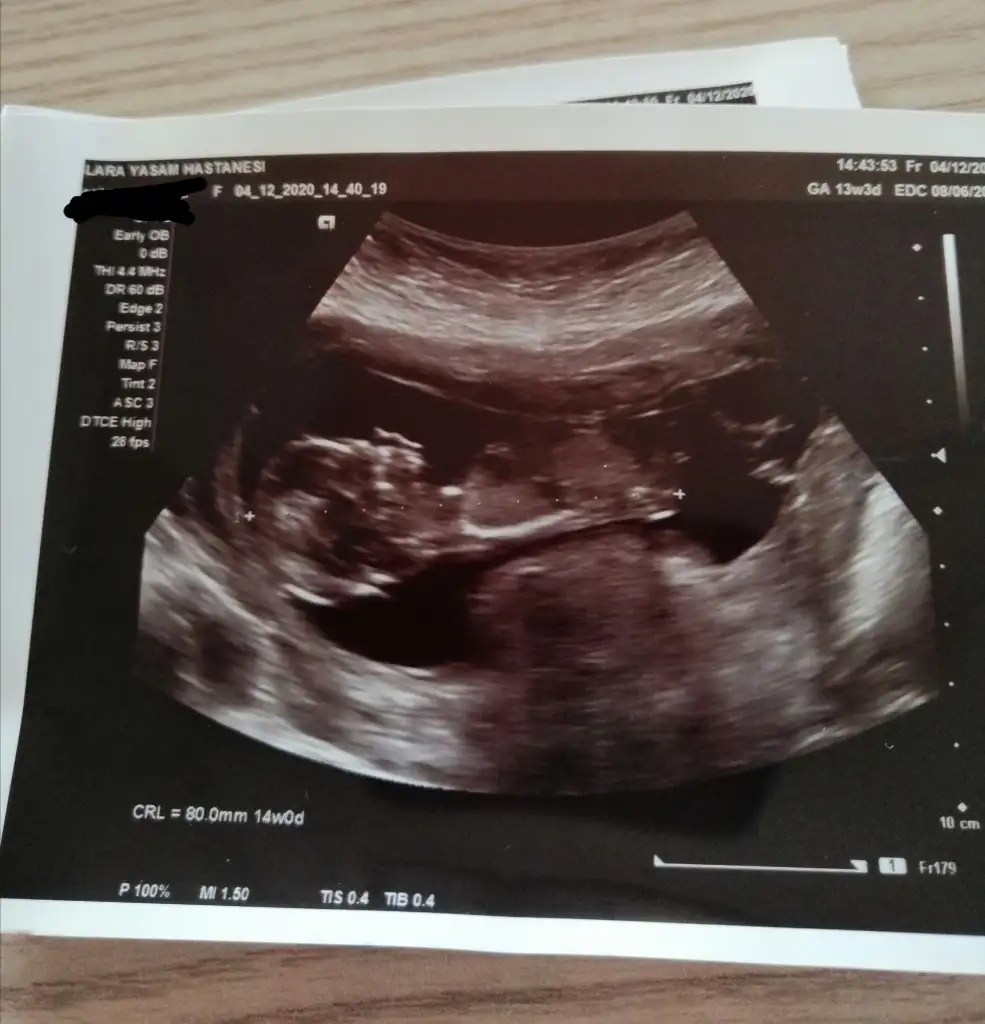

Ikra meyra Ikra meyra merhaba banada tahminde bulunur musunuz?🥰 ve anlayan diğer arkadaslarda tahminde bulunursa cok sevinirim😍

• 59BD2895-FA56-495D-AACF-4D76BE08FB8B.webp

59BD2895-FA56-495D-AACF-4D76BE08FB8B.webp

21,7 KB · Görüntüleme: 71